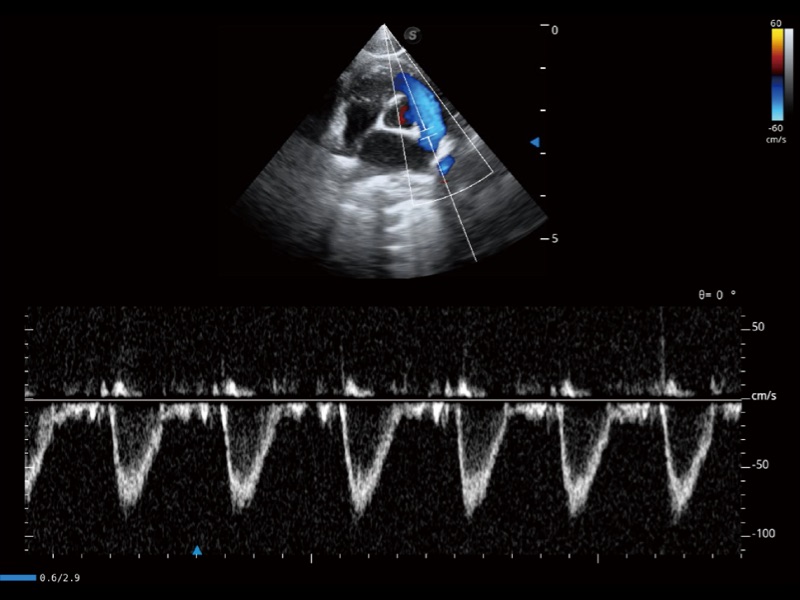

通過360度任意調(diào)節(jié)3條M型取樣線,在同一心動(dòng)周期上觀察心臟不同位置的運(yùn)動(dòng)曲線,得到準(zhǔn)確的心功能測(cè)量數(shù)據(jù),有效評(píng)估心肌運(yùn)動(dòng)及左心室功能。